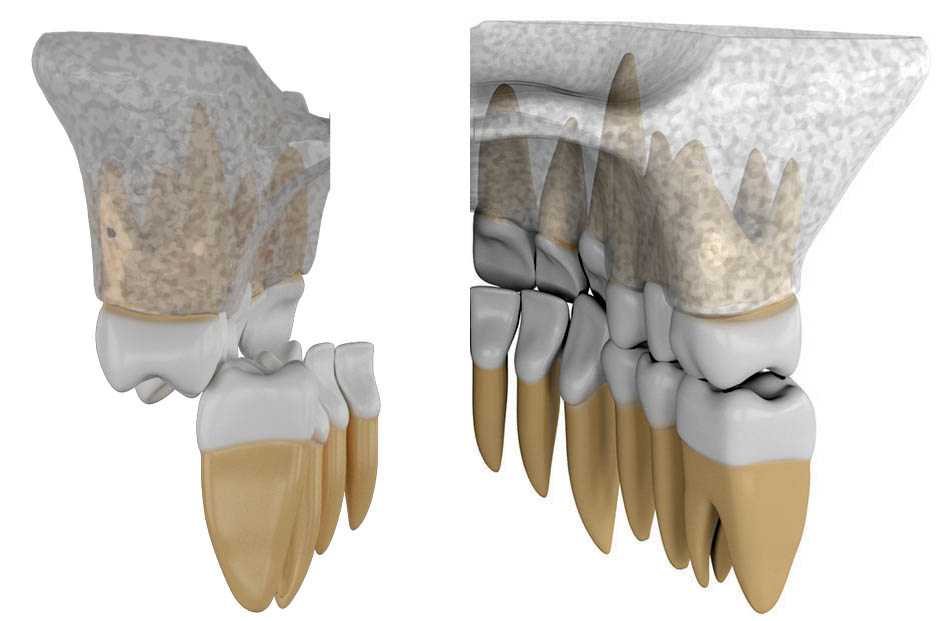

• بیمارانی که تنگی ماگزیلا دارند و به دنبال آن مندیبل هم تنگ شده است. البته کراس بایت خلفی نمیبینید چون هر دو فک تنگ میباشند. در این بیماران هنگام خندیدن کریدور باکالی کاملاً مشخص است (شکل 73-3). بعد از Expansion بالا قوس پایین هم باز میشود و ثبات هم خواهد داشت.

• بیماران دیپ بایت شدید مثل کلاسII/2 قدامیهای بالا به خاطر نیروی دیستاله کننده لبها رترود میشوند و به سمت عقب میروند (شکل 74-3) و بیمار دیپ بایت میشود. در بعضی بیماران سیستم عضلانی خیلی قوی است که نه تنها باعث جمع شدن دندانهای قدامی بالا به داخل میشود بلکه باعث میشود تا تحت فشار دندانهای قدامی بالا، دندانهای قدامی پایین هم جمعتر بشوند و در قوس کوچکتری قرار بگیرند. این حالت باعث تنگ شدن قوس پایین میشود. اگر دیپ بایت این بیماران را درمان نمایید، دندانهای پایین هم میتواند در قوس بزرگتری قرار بگیرند و عرض بین کانینی این بیماران بیشتر بشود که البته ثبات هم دارد.